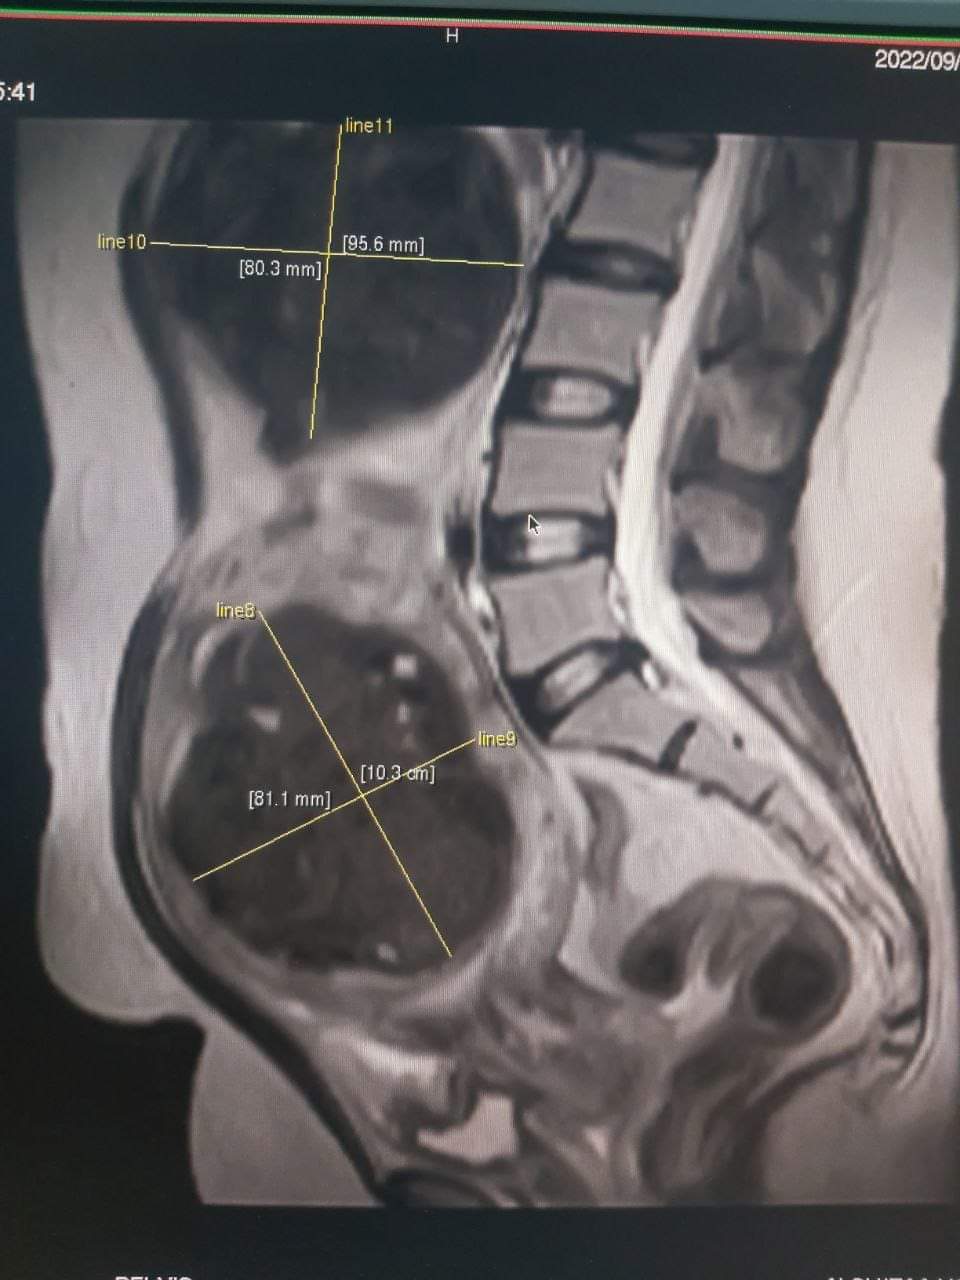

فحص رنين مغناطيسي لرجل يبلغ من العمر ٤٠ عام يعاني من آلام شديدة اسفل الظهر وبعد الفحص تبين ان لديه شظايا كبيرة الحجم قريبة من العمود الفقري ادت إلى ضغط على الحبل الشوكي وكذلك ضغط على الفقرة الرابعة والثالثة وكذلك ادت إلى تشويش العمود الفقري وايضا يعاني المريض من آلام حادة في الارجل والقدمين مع خدر الأطراف كما موضح في الصور ادناه